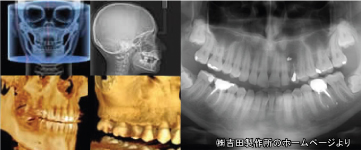

通常のレントゲンと比較してデジタルレントゲンは放射線量が非常に少ないため 小さなお子様やご高齢の方でも安心です。 |